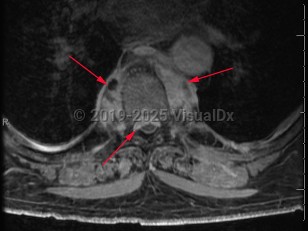

Collection of pus located around the spinal cord. Usually seen as a complication of vertebral osteomyelitis and discitis but may be related to hematogenous seeding during bloodstream infection. Frequently, the location of the abscess is in the epidural space. Patients may have acute or subacute back pain if this infection began as vertebral osteomyelitis or discitis. Fever may or may not be present. As the abscess forms, patients typically have focal and severe back pain. As the size of the abscess increases, it may impinge on the spinal cord, leading to signs of spinal cord compression, including motor weakness and sensory deficits. Untreated, the patient's neurologic symptoms can worsen to the point of paralysis.